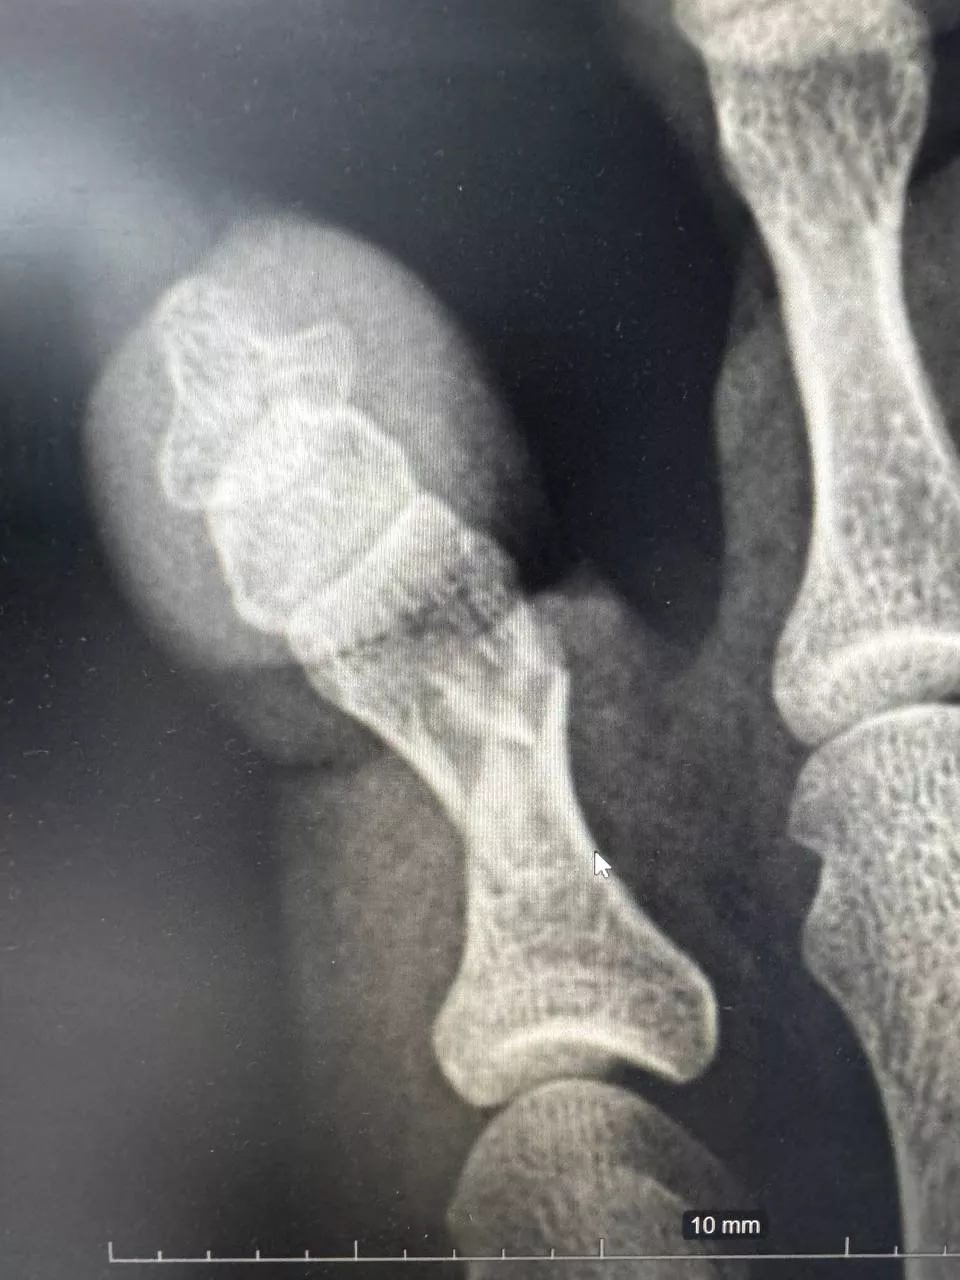

Осмотр и рентгенография позволили поставить диагноз — оскольчатый перелом проксимальной фаланги 5-го пальца. Иван Александрович выполнил репозицию (сопоставление) отломков кости и иммобилизацию стопы гипсовой лангетой. Контрольная рентгенограмма после процедуры позволила оценить результат и убедиться в восстановлении фрагментов. Пациентка довольная уехала домой.

Перелом пятого пальца левой стопы (1) и после репозиции кости и иммобилизации гипсовой лангетой